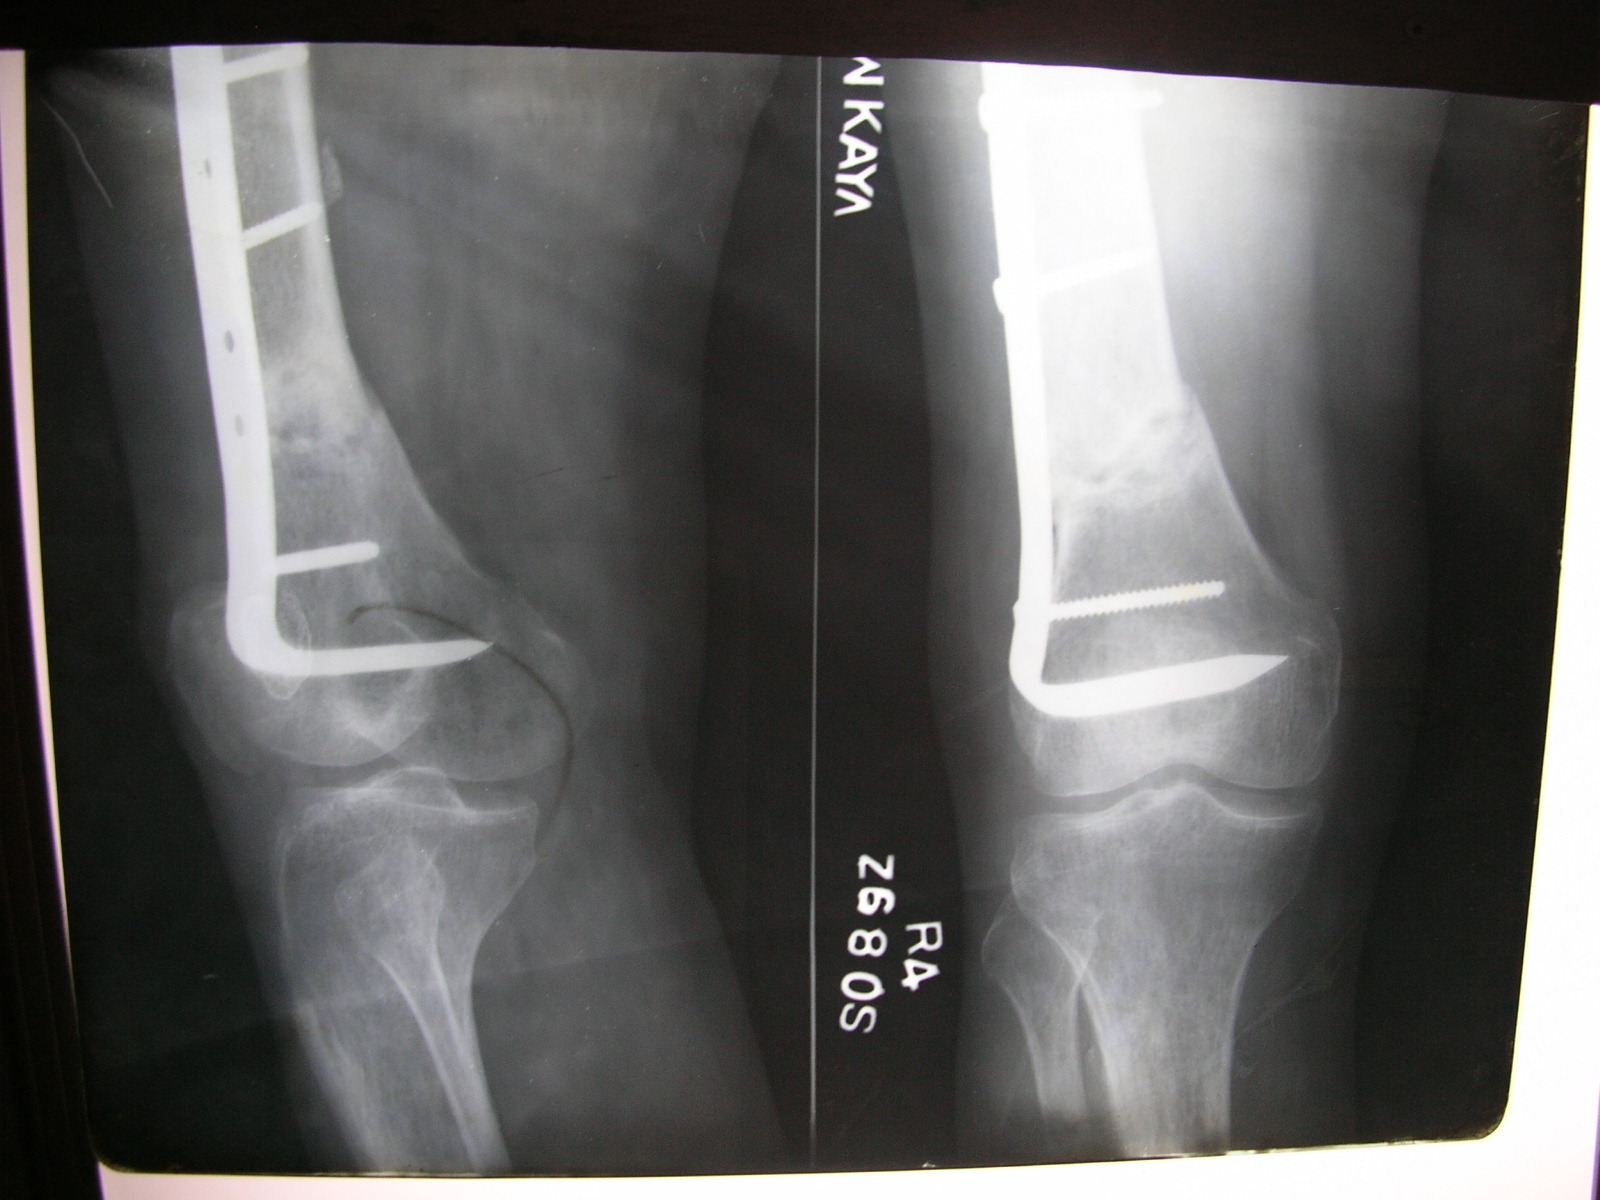

Xrays and Slides Nonunion of angled blade plate of supracondylar Angle Blade Plate Distal Femur In the proximal femur, the blade needs to be. Angled blade plates have a blade with a u profile and a fixed angle between the blade and the plate. Non‐surgical treatment, retrograde intramedullary implants, antegrade intramedullary implants. A triple drill guide is available, but this has been designed for the proximal femur and use with 130° angled blade plates: Randomized. Angle Blade Plate Distal Femur.